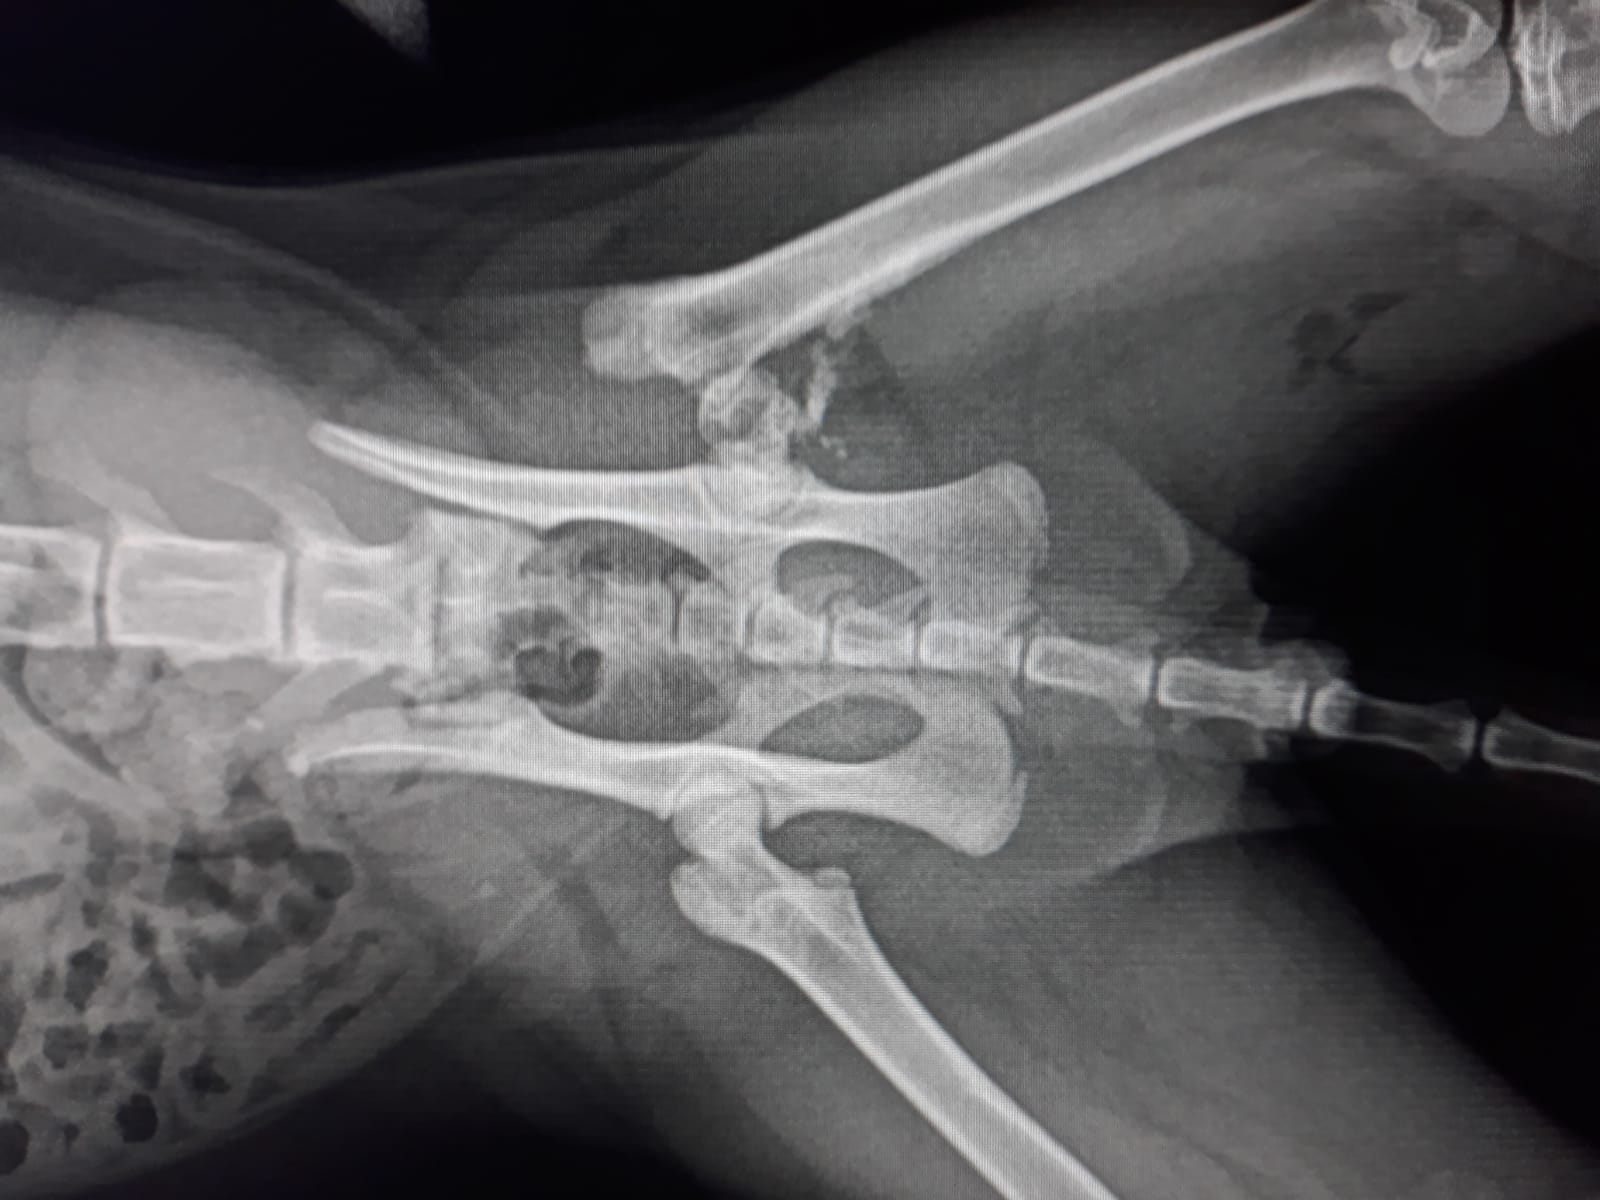

Urgency before Christmas! We have picked up this young cat from the colony next to the Mercadona Avda. Miguel Hernández. The poor boy has had an accident and now he has a fracture in his hind leg, as seen on the x-ray. It needs to be operated on to get him back on track and it will cost 200 euros! Please help us raise that money as soon as possible. Thank you